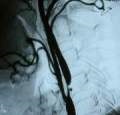

Vyšetření